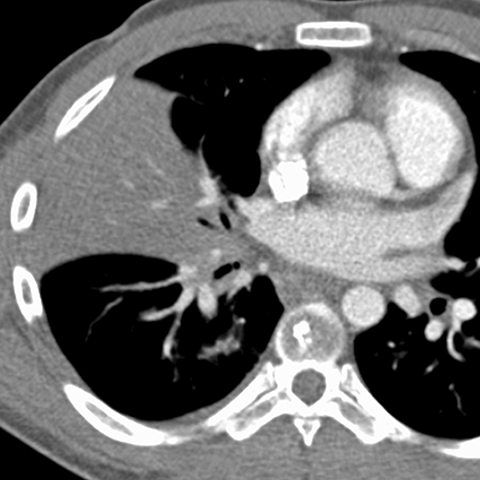

Silhouette Sign, RML Pneumonia (Chest CT) [4 of 4]